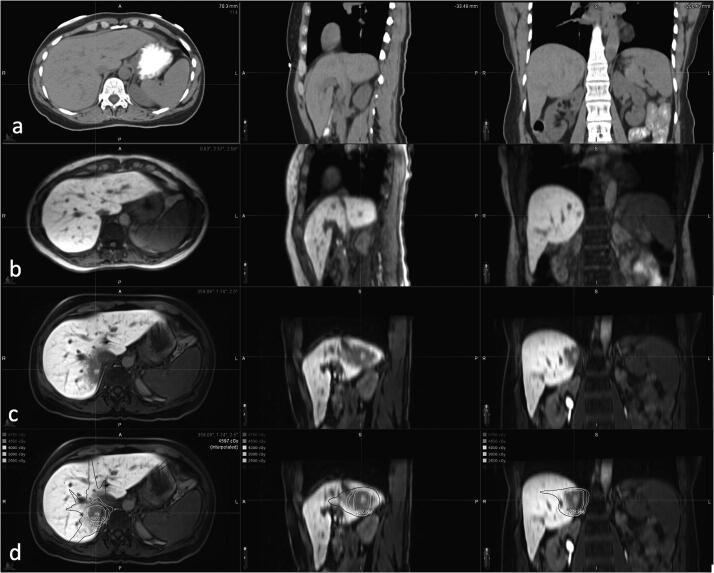

Eleven patients with abdominal malignancies were treated with free-breathing SBRT in three to five fractions on a 1.5 T MR-Linac. Online adaptive plans were generated using Adapt-To-Position (ATP) or Adapt-To-Shape (ATS) workflows based on motion averaged or mid-position images derived from a pre-beam 4D-MRI. A high performance server positioned on the local MR-Linac machine network was utilized for 4D-MR image reconstruction. A parallel contour editing approach was employed in the ATS workflow. Intravoxel incoherent motion (IVIM) and T2 mapping sequences were acquired during adaptive planning in both ATP and ATS workflows for treatment response monitoring. Adaptive plans were delivered under real-time cine image motion monitoring.

The shortest 4D-MRI time-to-image was the motion averaged image, followed by mid position and respiratory binned images. In this cohert of patients, 50% of treatments utilized the ATS workflow; the remaining treatments utilized the ATP workflow. Mid-position images were utilized as daily planning images for two of the eleven patients. The mean daily adaptive plan secondary dose calculation and ArcCheck 3D Gamma passing rates were 97.5% (92.1-100.0%) and 99.3% (96.2-100.0%), respectively. The median overall treatment times for abdominal SBRT was 46 and 62 min for ATP and ATS workflows, respectively.